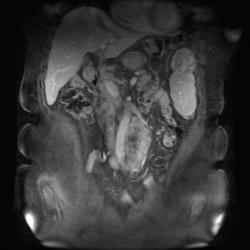

Диффузионно-взвешенные